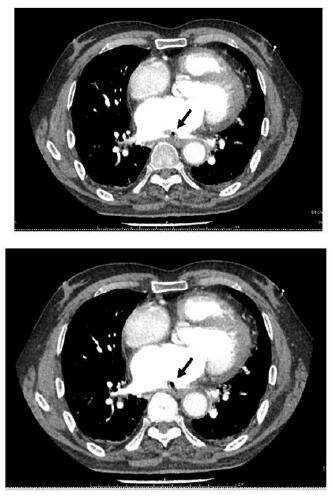

1 资料与方法患者,男,68岁;因“间断胸闷心慌1个月余,呕血伴发热1 d,意识障碍12 h”收入华中科技大学同济医学院附属同济医院。患者一个月前自觉胸闷、心慌,至当地市级医院诊断为“房颤、冠状动脉粥样硬化”,入院前34 d行房颤消融术+冠脉造影术,术后口服达比加群酯110 mg 2次/d,术后3 d再次因胸闷心慌至当地县人民医院住院治疗,给予对症治疗,症状可缓解。入院2 d前再次出现胸闷心慌等不适,入院前1日下午4时呕血约300 mL,伴寒战高热,最高可达39.5 ℃,并于入院当日中午12时出现意识障碍,言语不清,为求进一步治疗转至本院急诊科。急查头部CT示:脑萎缩,脑白质病;右侧半卵圆中心及左侧基底节区片状低密度影,考虑为缺血梗死灶;右侧小脑半球片状低密度影,考虑脑梗死、软化灶形成。后患者意识障碍较前缓解,急诊科收治入院。既往史:高血压史十余年,5年前脑梗死病史,10年前行腰椎间盘突出手术治疗,吸烟30余年,每日一包,饮酒30余年,每日250 mL,戒酒10年。入院体格检查:患者意识清醒状态,言语沟通不畅,心电监护提示:血压105/80 mmHg,脉搏87次/min,SPO2 100%,心率18次/min;双侧瞳孔等大等圆,直径2.5 mm,对光反射存在,双肺呼吸音粗, 未闻及啰音;心音可,律齐,未闻及杂音;腹软,移动性浊音阴性,肠鸣音正常。四肢无畸形,四肢活动无障碍,双下肢无水肿,生理反射存在,双侧巴氏征阳性可疑。患者入院后完善相关检查。血常规:白细胞计数23.23×109/L,血红蛋白93.0 g/L,血小板计数117.0×109/L,谷丙转氨酶14 U/L,谷草转氨酶17 U/L,尿素15.93 mmol/L,肌酐103 μmol/L,葡萄糖10.84 mmol/L,N-末端脑利钠肽前体(N-terminal pro brain natriuretic peptide,NT-proBNP)5 577 pg/mL,降钙素原32.51 ng/mL,高敏心肌肌钙蛋白I 413.9 pg/mL,血乳酸2.22 mmol/L。心脏超声检查示左房扩大55 mm,心脏收缩力下降,左心EF值40%。患者入院后给予抗感染、抑酸、营养支持等治疗,患者于入院当晚9时出现剧烈咳嗽,后意识障碍再次加深,遂行颅脑CT检查,示左侧大脑内气体栓塞(图 1);神经内科会诊,考虑脑内气体栓塞。给予患者头低脚高位,降低颅内压等治疗,次日晨复查胸部增强CT,示左房改变,考虑左房破食管瘘并左房血栓形成(图 2),诊断为“心房食管瘘”,请胸外科会诊意见:患者颅脑内积气吸收后,可进行心脏食管手术。患者于入院第2天上午8时出现呼吸衰竭,行气管插管术,呼吸机辅助呼吸,患者家属于当日下午因个人原因办理出院。

| 不同层面内左心房内低密度影,考虑心房食管瘘后气体残留,周围有血栓形成(黑色箭头示) 图 2 患者胸部增强CT结果 |